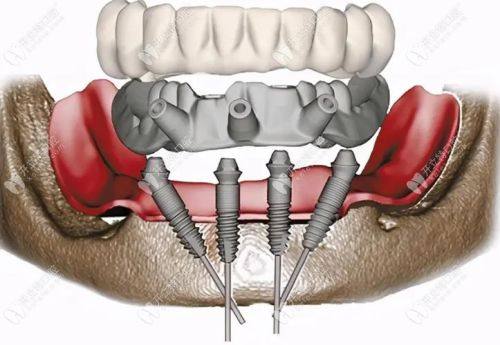

种植牙:耿永铅医生擅长各类种植牙诊疗项目,可根据患者的口腔条件选择适配的种植体类型,如韩国登腾、美国皓圣、德国xive、瑞典astra等,也可运用穿翼板种植牙技术针对牙槽骨条件不佳的患者开展诊疗,帮助患者修复良好的咀嚼功能与口腔美观度。

能够熟练运用多种种植牙相关技术,包括穿翼板种植牙技术等,针对牙槽骨吸收重度、骨量不足的患者也可提供适配的种植解决方案。术前依托医院的数字化牙科影像系统精细测算种植位置与角度,保护手术操作的精细性,减少术中创伤,提升术后修复效率。